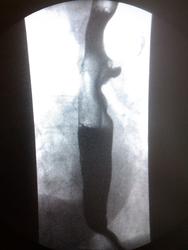

Пациентка, 74 года. Операция по поводу дивертикула пищевода лет 25 назад. Нужны мнения!

Ахалазия кардии, скользящая грыжа пищеводного отверстия диафрагмы, мелкий дивертикул с/3 пищевода - это мнение.

Тракционный дивертикул пищевода. ГПОД. Эзофагоспазм. За ахалазию сомнительно. А вот почему пищевод такой широкий - стоит задуматься.

Может быть он гипотоничный + третичные сокращения вот и выглядит широким, возможно там и эзофагит.

Я такие широкие пищеводы вижу регулярно при склеродермии, например. И клиницисты как бы должны знать о ее существовании, например же. Наше дело - констатировать факты, а их интерпритацию стоит все же оставить другим докторам.

"Нужны мнения!" Мнение: плохо оперировали тогда или: не причину, а следствие. Дивертикул есть и лит есть. ИМХО. А где причина - коллеги по поводу дистального отдела отд. пищевода  уже писали. Теоретически - проблема с 12п. кишкой( по Витебскому)